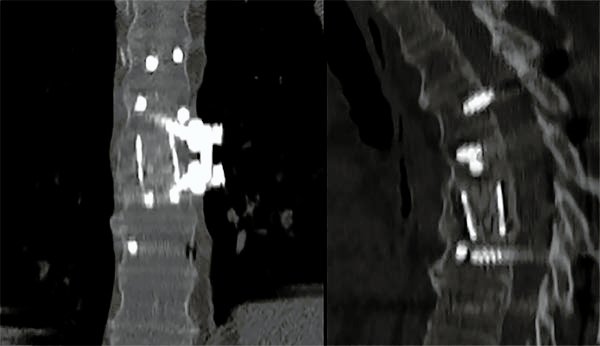

Figura 3:

Caso 24. A: Fractura L1: B1; N1. B: Control 7 meses que evidencia consolidación. C y D: Retiro de osteosíntesis a los 9 meses con buena movilidad en las radiografías dinámicas de control.

Figura 7:

Caso 8. Control postoperatorio alejado del paciente con un buen callo de fusión, sin pérdida de corrección.